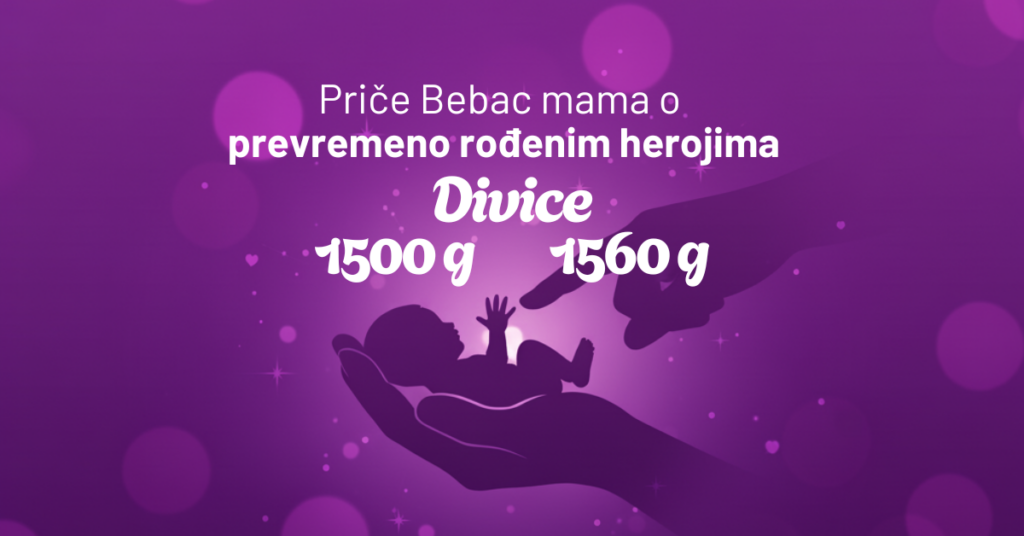

Svaka buduća mama razmišlja i proživljava svaki sekund, svaki bebin minut dok je u stomaku. Do skoro je teško bilo i zamisliti kako uopšte izgleda razvoj tog malog života, no savremene tehnologije sada to menjaju.

To čudo prirode, otelotvoreno u nastanku života tokom 40 nedelja, moguće je sada videtu u kratkom video-snimku u trajanju od četiri minute. I bukvalno se vidi svaki detalj, sve te fantastične promene na trudnici, ali i u njoj – od začeća pa do porođaja.

Tih promena mame obično nisu ni svesne, katkad traju bezgranično, ali kada se ceo taj period sažme u samo četiri minuta, rezultat je impresivan i apsolutno nikoga neće ostaviti ravnodušnim.

A kako izgleda kada cela trudnoća od devet meseci? Evo, baš ovako.